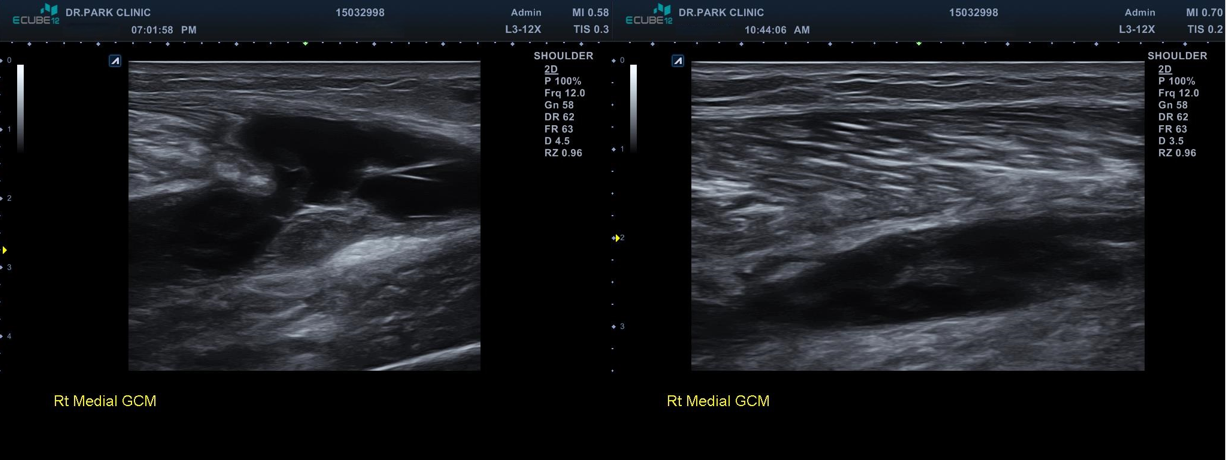

초음파 검사를 하니 근육 파열을 더 자세히 확인할 수 있습니다. 근육은 각각 근막으로 둘러쌓여 있고 이게 근육과 근육을 얇게 구분해주고 있는데요, 근육이 찢어지면 보통 이 근막이 벌어지게 됩니다. 이 환자분도 근막이 벌어지는 근육파열 양상을 보이고 있습니다

다시 촬영한 초음파 검사는

근육 파열이 훨씬 심해지고 근막이 다 벌어지면서 피가 고여있는 모습을 보이고 있습니다.